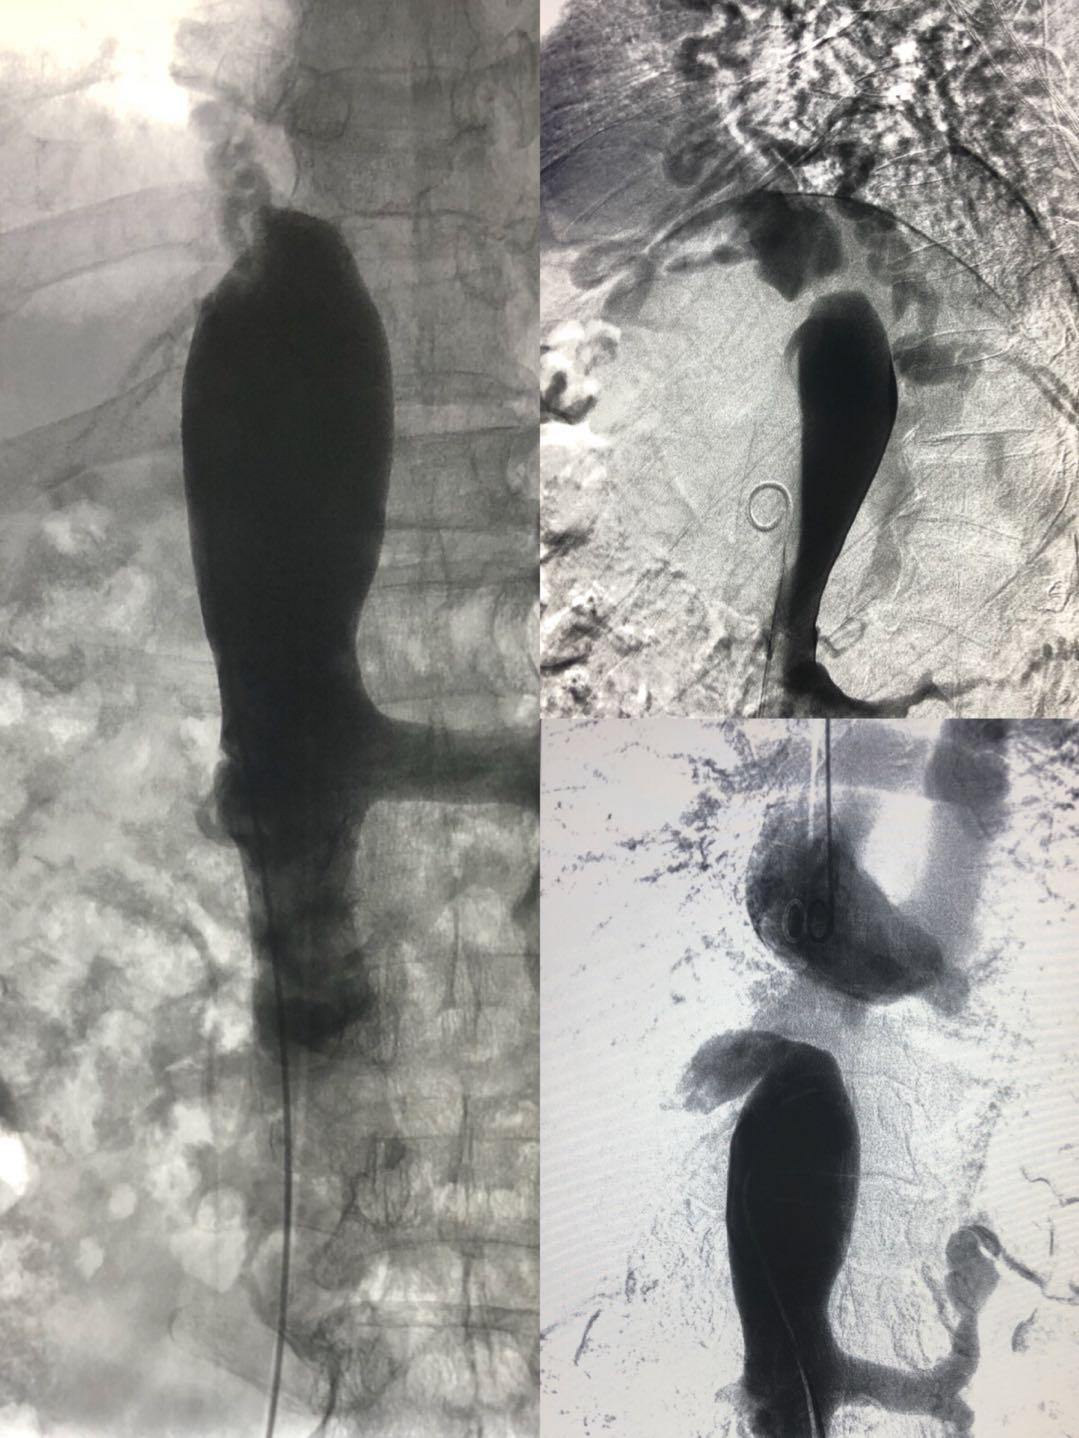

8月31日早8:15,介入科李建国主任、何彤副主任在局麻下对患者实施了经右侧颈静脉、右侧股静脉上下入路穿刺,对端造影,利用导管导丝成功打通下腔静脉闭塞段。再选用不同型号球囊分次扩张,在全体医护人员的密切协作努力下,闭塞的下腔静脉终于通畅,手术历时1小时15分钟,患者生命体征平稳安返病房,进一步的康复中。

布-加综合征首选介入手术治疗,该手术是介入医生在DSA的透视监视下利用穿刺针、导管导丝、球囊等一系列器材对患者进行的微创治疗,手术能迅速打通下腔静脉闭塞段,显著降低下腔静脉回流右心房的阻力,可有效减少食管胃底静脉曲张再出血和腹水复发等肝硬化并发症,使患者下肢溃烂得到逐步改善。手术时间短,不需开刀,患者全程清醒无痛苦,创伤小、效果好,能为此类患者快速有效解除病痛折磨。